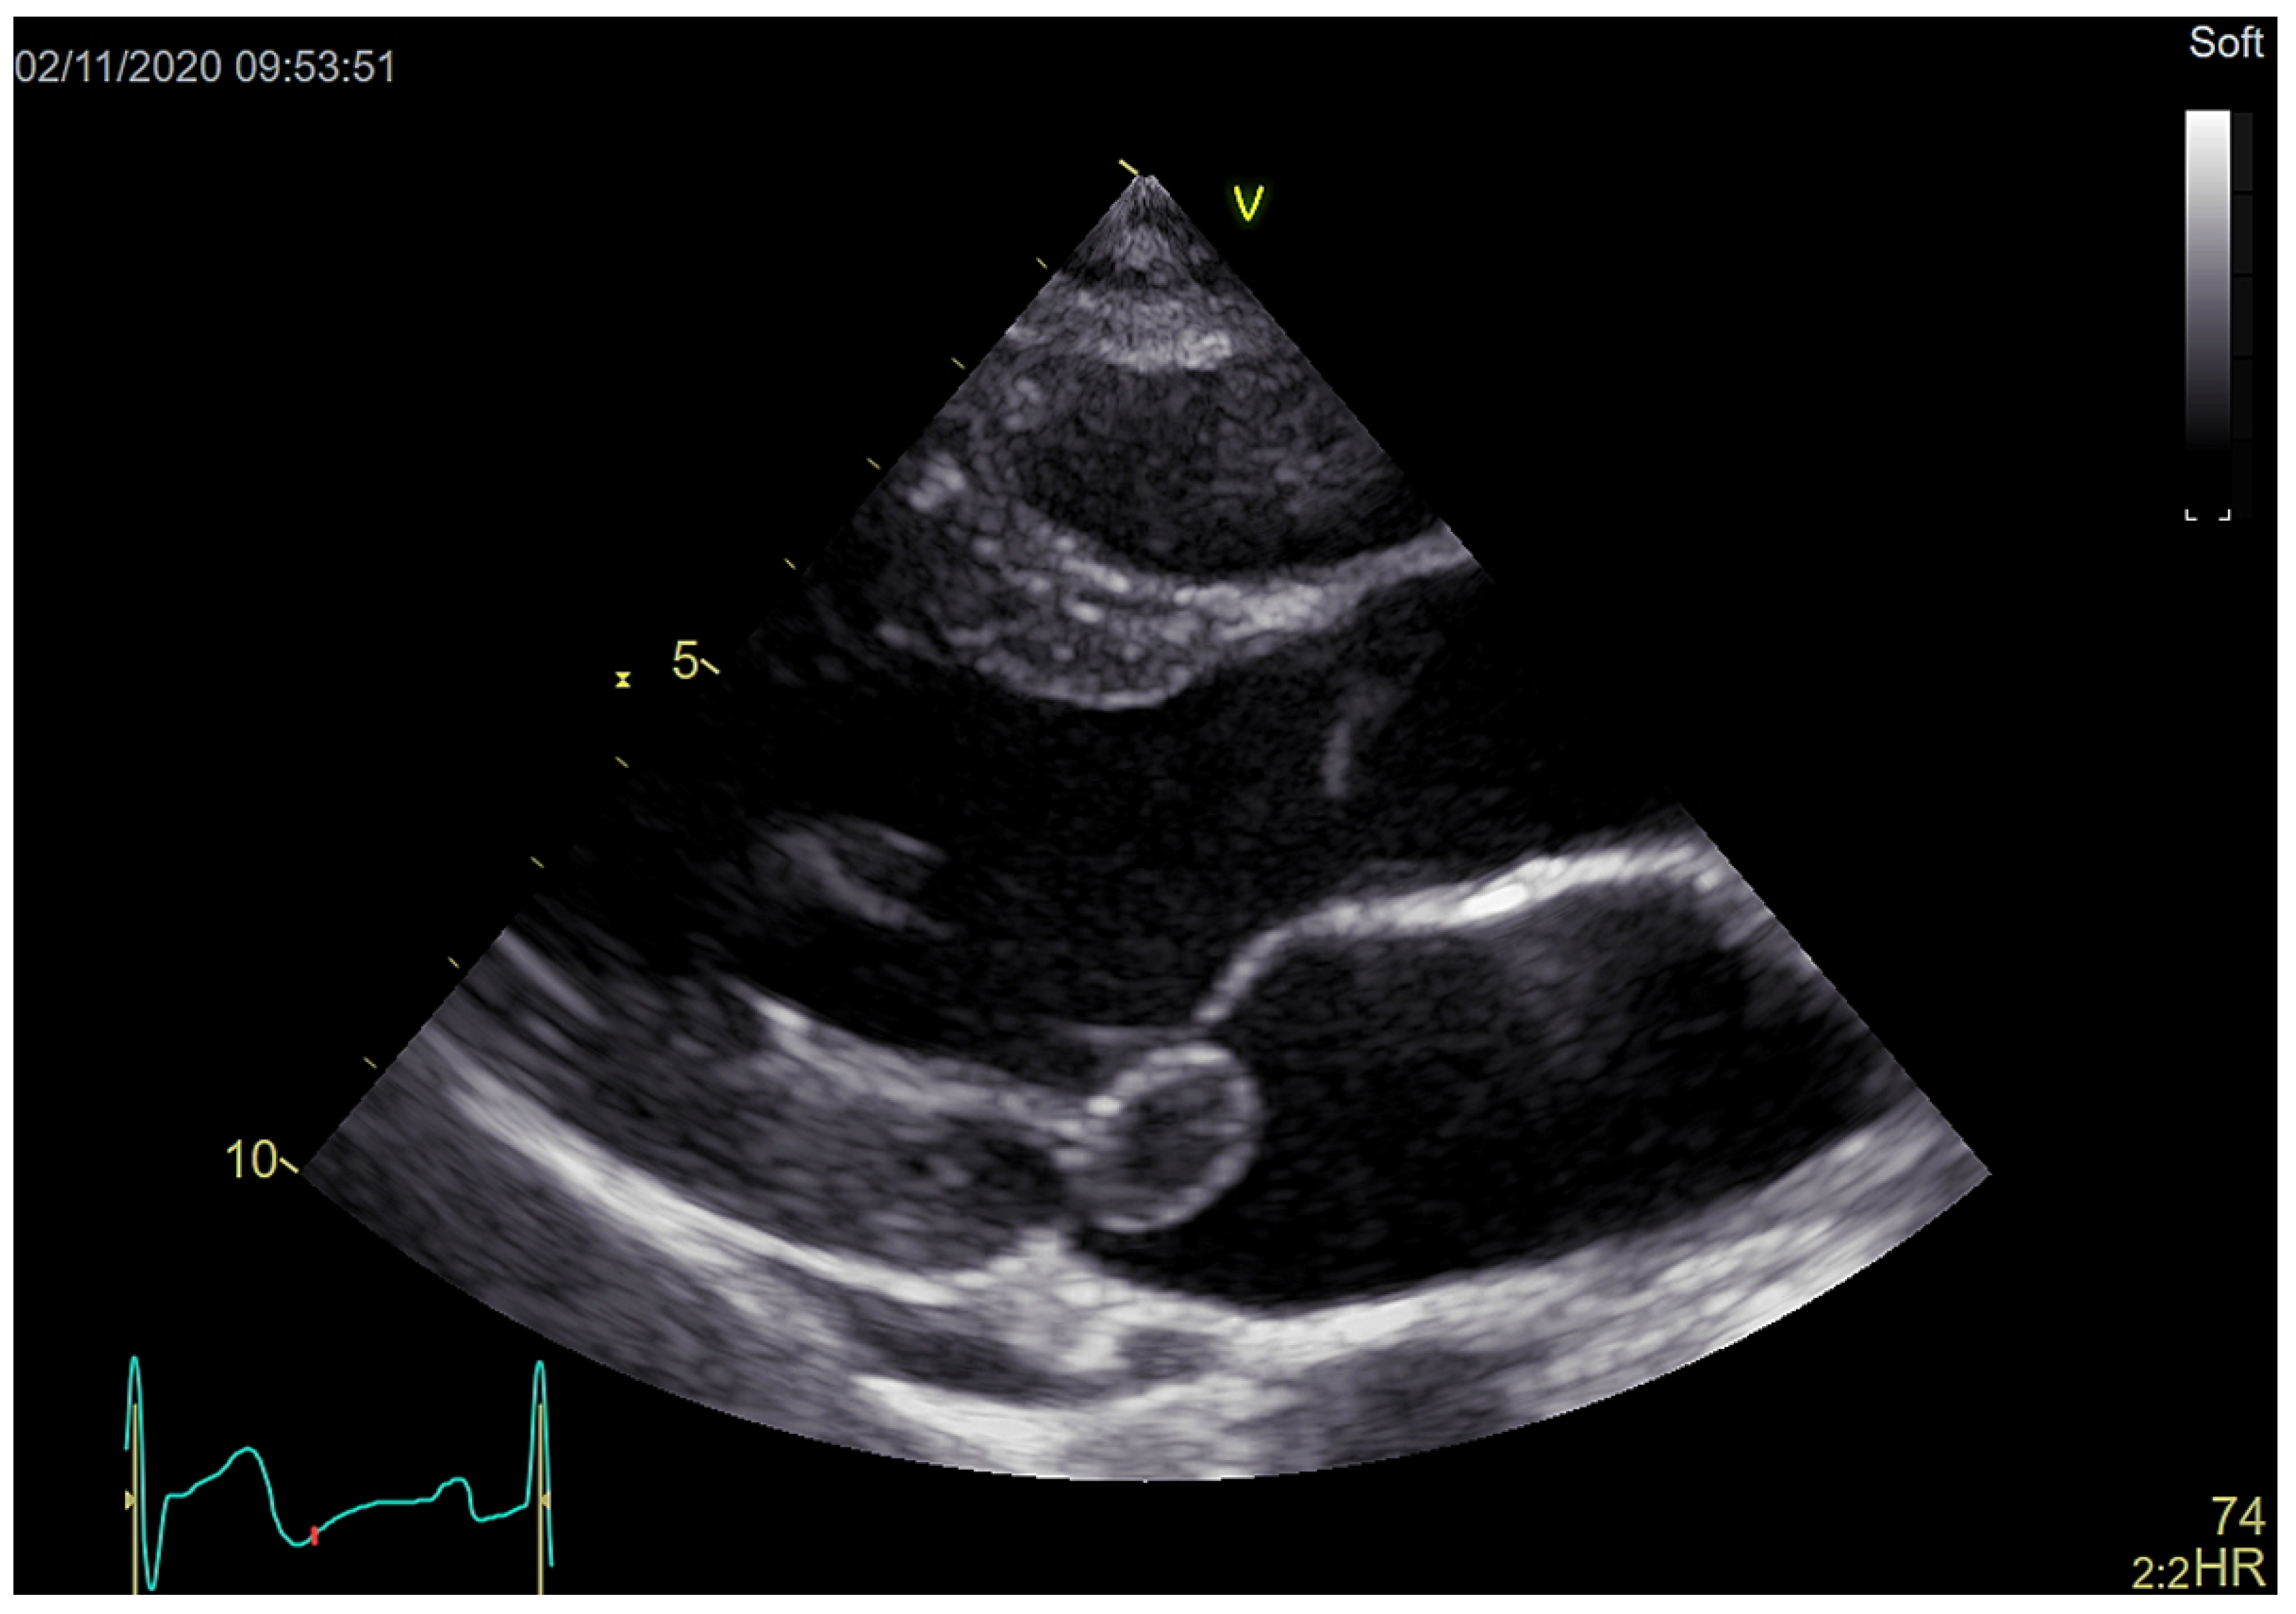

Large Native Mitral Valve Vegetation in a Previously Healthy 19-Year-Old Woman